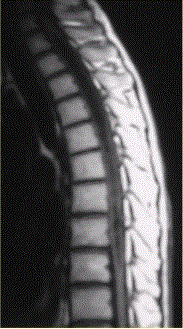

问题 患者女,45岁,胸部不适。影像学检查结果如下图所示。 病变的诊断为

选项 A.星形细胞瘤 B.室管膜瘤 C.脊髓空洞 D.髓内寄生虫 E.成血管细胞瘤 F.脊髓内转移瘤

答案 E